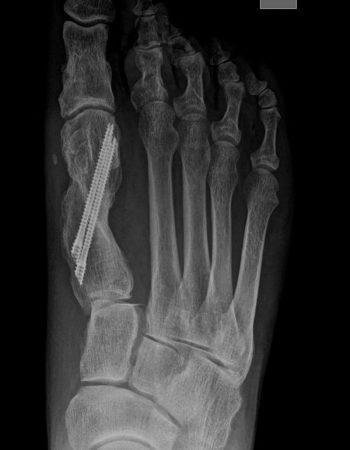

El caso que presentamos es muy representativo de la capacidad de corrección de la cirugía percutánea de tercera generación en la deformidad de Hallux Valgus. Se trata de una paciente con dolor a nivel del bunion y metatarsalgia con un 2º dedo sobre el primero que también le causa intolerancia con el calzado. Fue sometido a una técnica percutánea llamada MICA (Minimal Invasive Chevron Akin), sin ingreso y permitiendo carga inmediata

En las imágenes radiográficas se observa cómo se consigue una gran corrección en la posición de los dedos y una reducción de los sesamoideos sobre la cabeza metatarsiana. La fijación con tornillos nos va a permitir mantener esa reducción y estabilizar el montaje para reducir el dolor postoperatorio y permitir una buena consolidación ósea, como se ve en la última imagen.